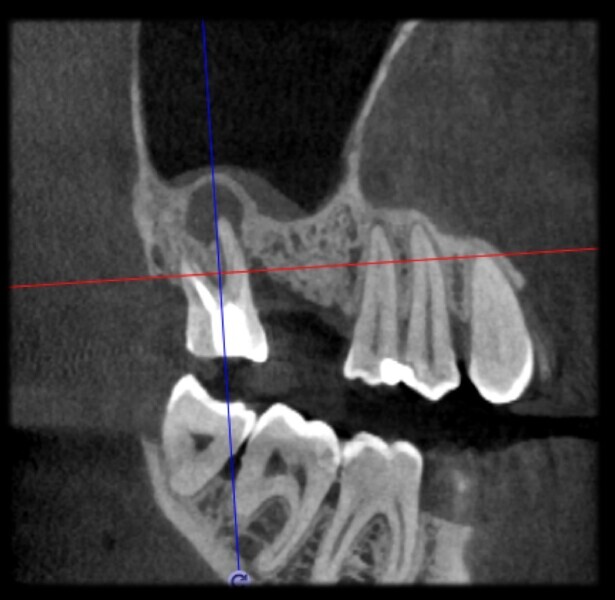

Use of 3D technology in the diagnosis and treatment of endodontic disease